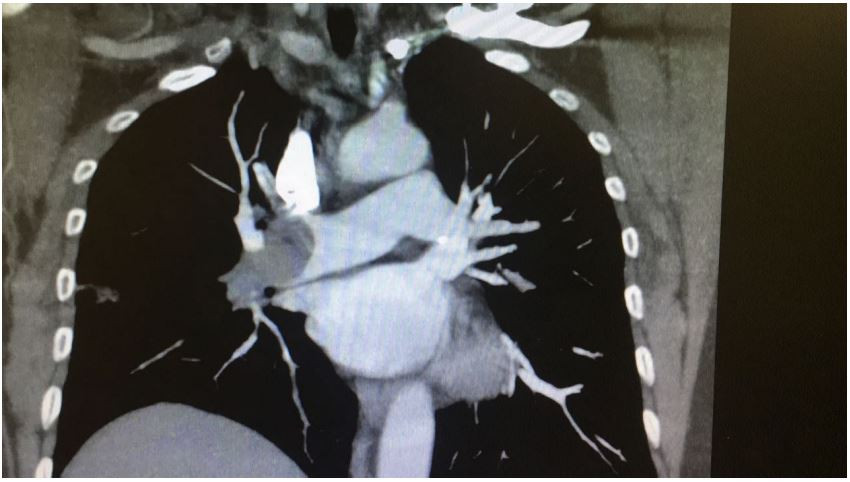

Homem, 58 anos, tabagista, é admitido na unidade de emergência com queixas de dor torácica anterior e dispneia intensa há 30 minutos, de início súbito. Encontra-se taqui-dispneico, sudoreico e agitado. Murmúrio vesicular presente, sem ruídos adventícios, frequência respiratória – 38 irpm, ritmo cardíaco regular, sem sopros ou bulhas acessórias, frequência cardíaca – 132 bpm, pressão arterial – 62X32 mmHg. Saturação de oxigênio (em ar ambiente) = 78%. O eletrocardiograma mostra apenas taquicardia sinusal. Realiza a seguinte tomografia computadorizada de tórax:

Qual a melhor conduta neste caso?